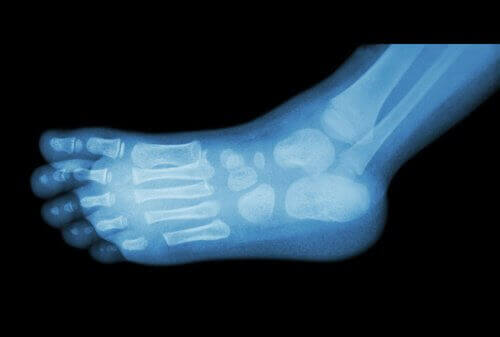

De arts kan een eenvoudige röntgenfoto maken om hielspoor te diagnosticeren.